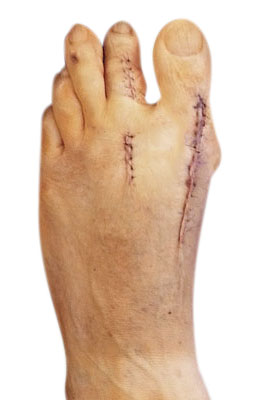

Before

After

Lapidus Forever Bunionectomy™

Jeanne is a 54-year-old active athlete who was training for a triathlon until her foot gave out. He has blisters and pain on her bunion from her lack of proper shoe fit. We performed our Lapidus Forever Bunionectomy™ and kept Jeanne training throughout her recovery process. Jeanne completed a triathlon just 12 weeks post-surgery and had no pain at any time after her surgery.

“After picture” taken at first post-op visit five days post-surgery.